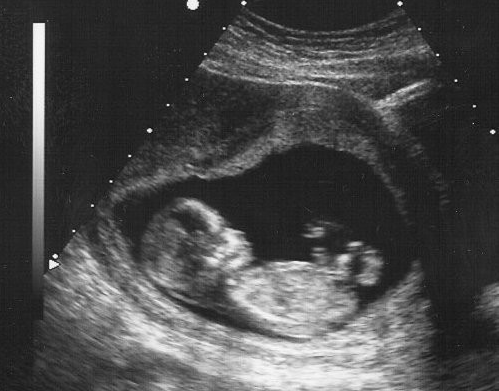

Yeni bir haftaya başladık ve senin aklında bana dair bir sürü soru var mesela 11 haftalık gebelikte bebeğin boyu ne kadar olur. 11 haftalık 77 günlük 2 ay 17 günlük hamile oluyorsunuz. Hafta bebeğin en hızlı şekilde geliştiği haftadır bebeğinizin başı normalde bu haftaya kadar gövdesine göre büyüktü ancak 11. Trimesterin son ayındasın demektir.

Birgül raim 3 yıl. 11 haftalık bebeğin boyu ve kilosu. Dış kulak yolu ve kulak zarı da 11. Anne karnında 11 haftalık bebek gelişimi ne durumda gebelikte 11.

Haftada bu baş vücut oranı artık normale yaklaşmaya başlıyor. Gebelikte 11 haftasında bebeğin el ve ayak tırnakları oluşur. 11 haftalık gebelik kaç aylık olur sorusunun cevabı şudur.